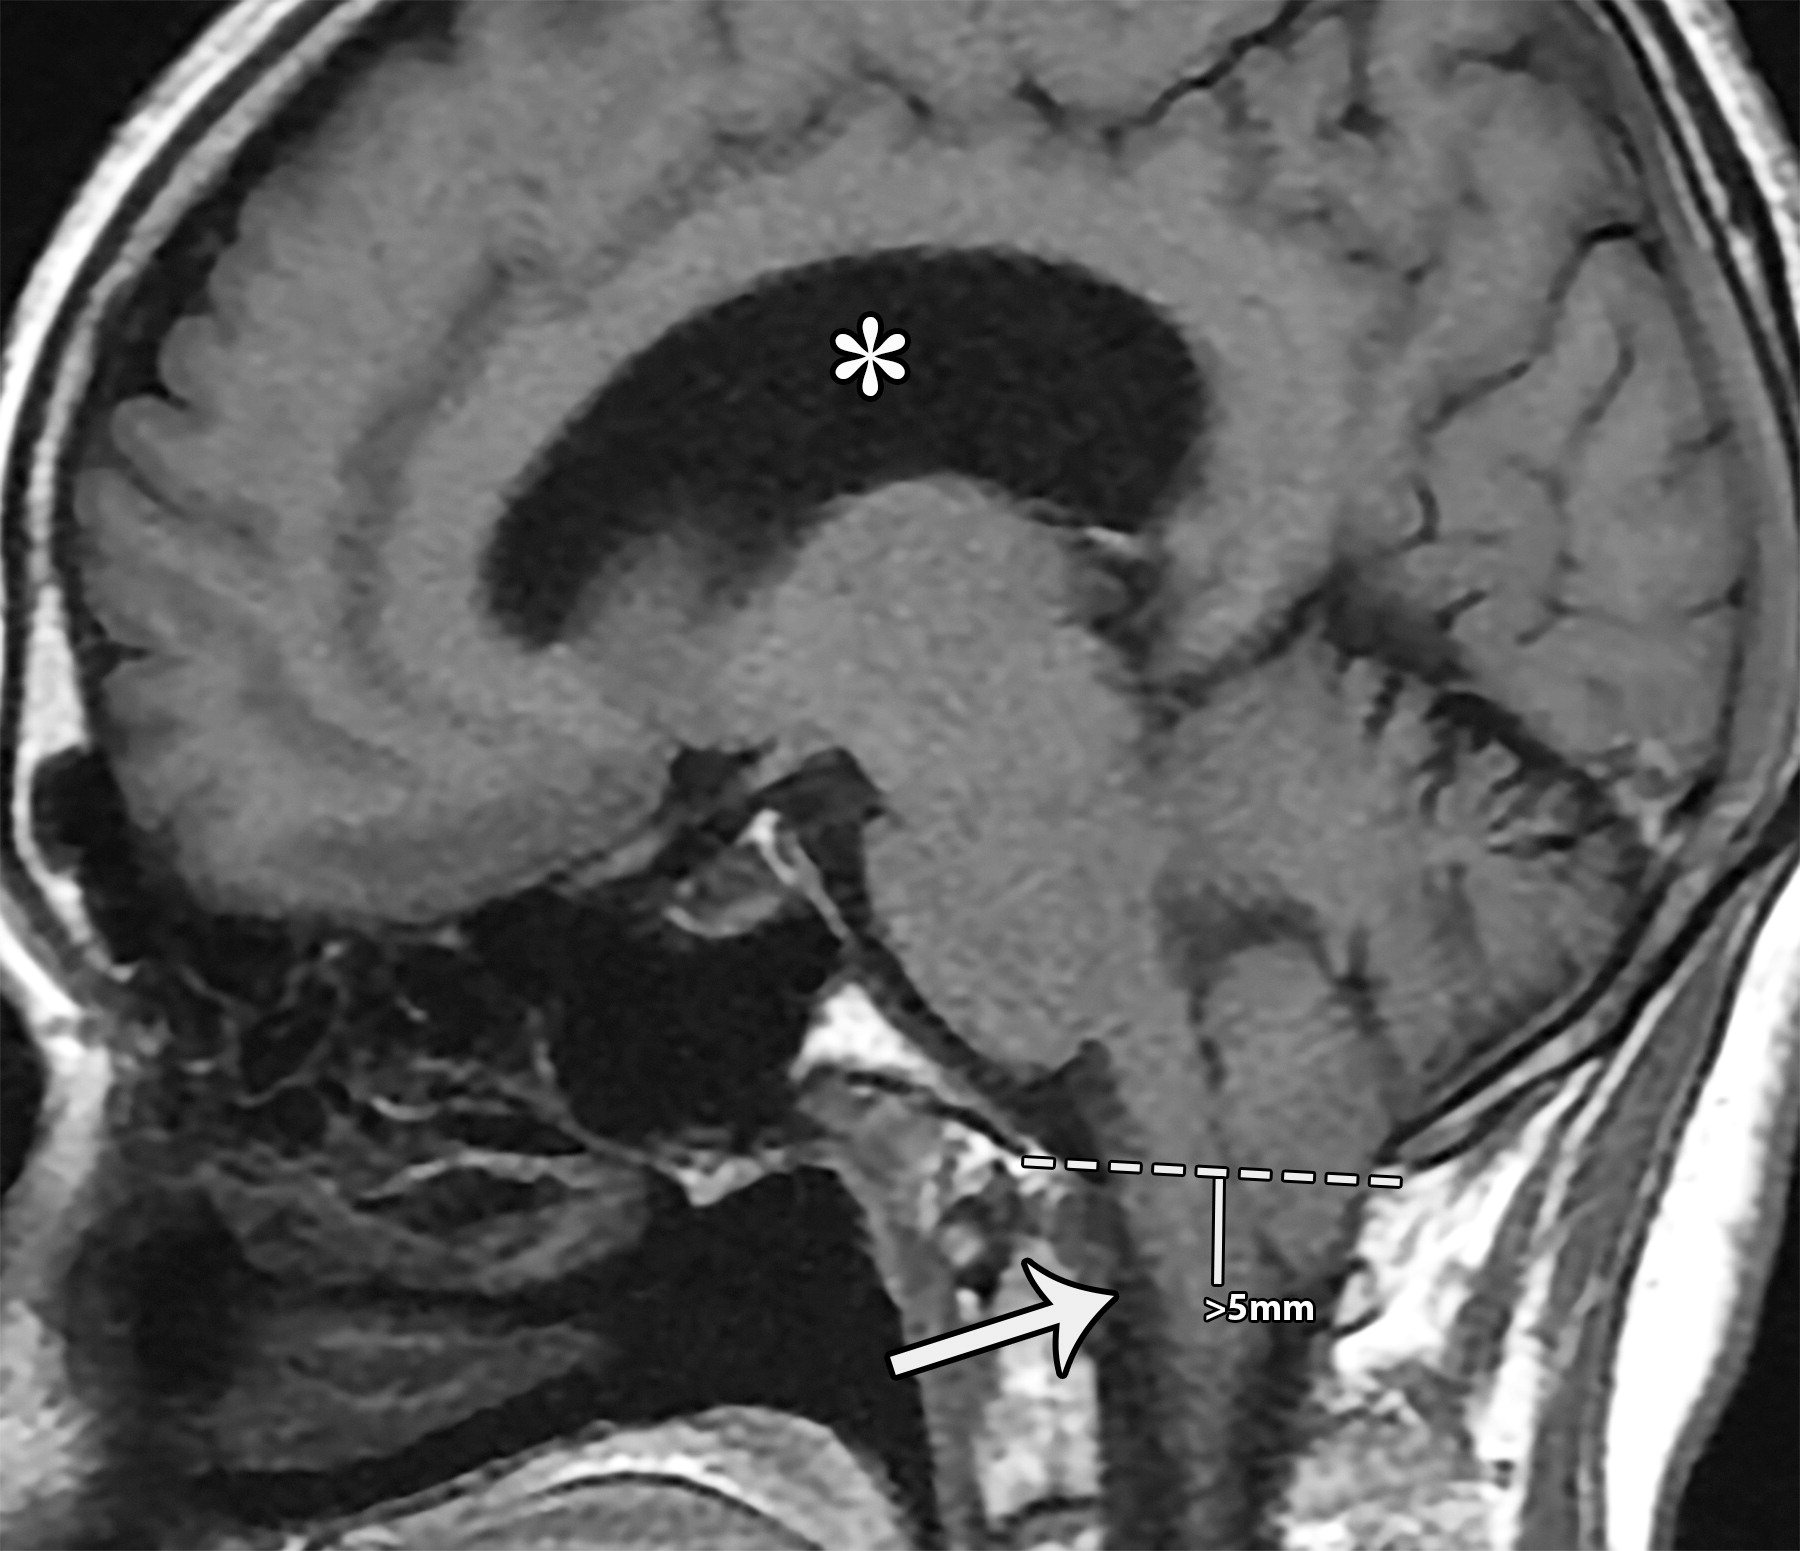

04195f077fedbc1c48a7bdd1f903932f.jpeg

相比于McRae线(白色虚线),小脑扁桃体向下移位(超过5毫米),注意枕大池闭塞,延髓向前移位(白色长箭头)以及脑积水(白色*)

ada0d28046f51452ac0893532b2d281e.jpg

Chiari畸形Ⅰ型。小脑扁桃体下降(b图中白色弯曲箭头),伴脑干向前移位(a图白色长箭头),以及枕骨大孔脑脊液的闭塞(a图中白色短箭头)。